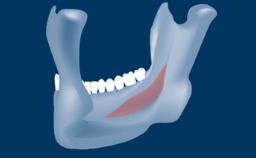

Lateral Sinus Floor Elevation

Following tooth loss, alveolar resorption and ongoing pneumatization of the maxillary sinus may lead to vertical and horizontal bone deficits in the posterior maxilla.

This deficit reduces the distance between the maxillary sinus floor and the alveolar process, so that reconstructing the vertical bone height by means of a sinus floor elevation procedure may be a prerequisite for placement of dental implants of the correct dimensions and in the ideal three-dimensional positions in order to achieve optimal functional and esthetic treatment outcomes while respecting relevant anatomical structures.